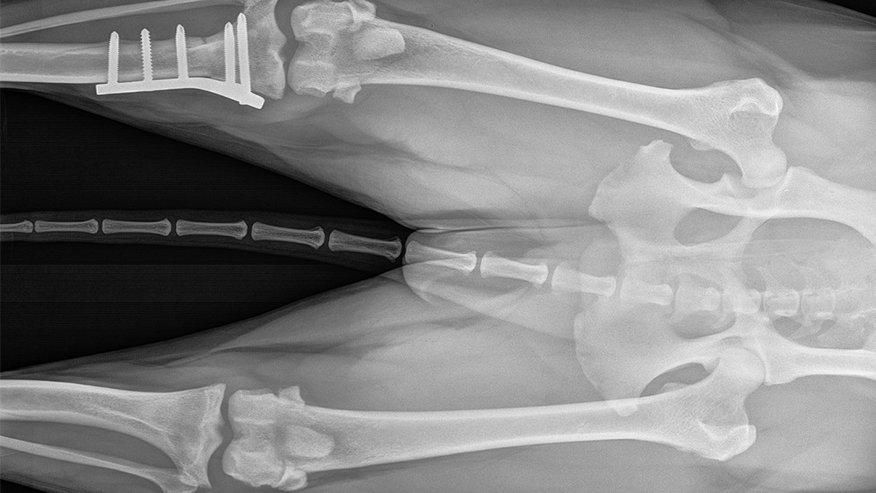

• 876x493 pet medical center BoneJointSurgery

Orthopedic surgery involves surgery of the bones, joints, muscles, tendons, and ligaments. Fractured bones and torn ligaments are some of the most common injuries seen by the veterinary surgeon. In many cases.... Read more

• 876x493 pet medical center TPLO

Our hospital offers a wide range of Orthopedic Surgery services to cope with a wide range of injuries and conditions. In the case of a broken leg, for example, our surgeons can perform such procedures as bone plating, pinning and/or wiring to successfully mend the fractured bones. On the other hand, if your pet experiences a knee ligament injury, procedures such as a TPLO (Tibial Plateau Leveling Osteotomy) or extracapsular repair may be recommended.... Read more